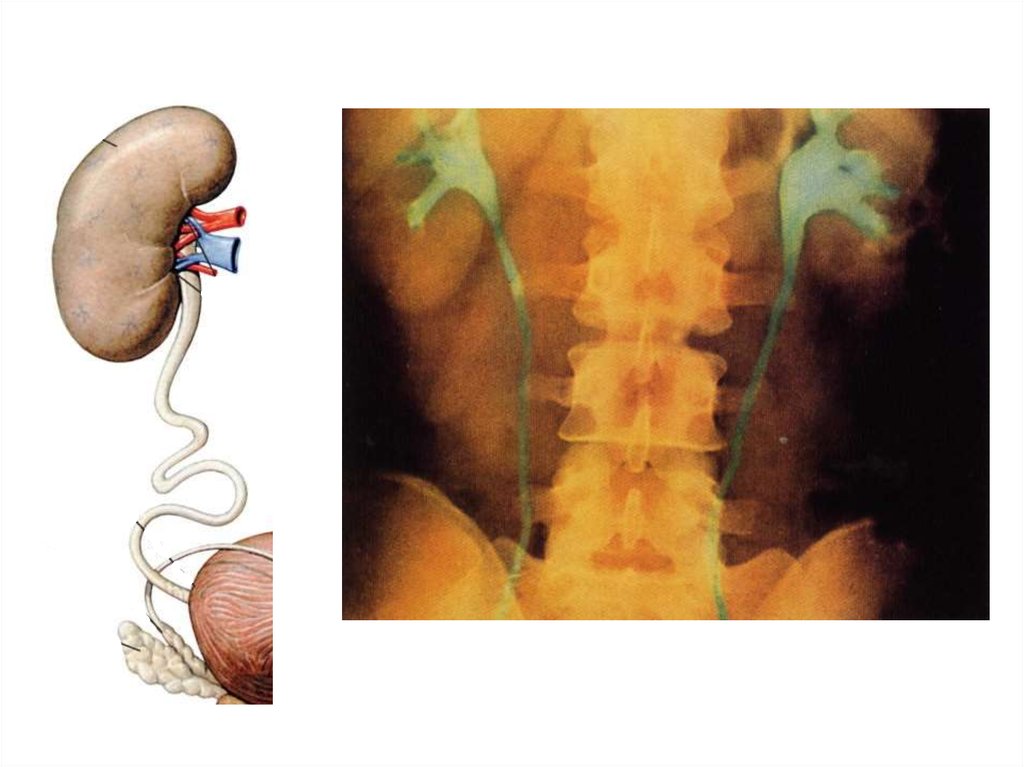

Мочевыделительная система